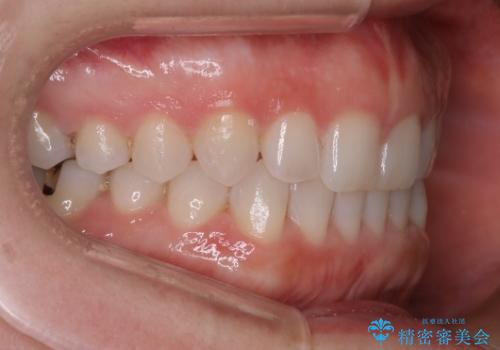

- 前歯の正中離開(すきっ歯)の改善を希望され来院された患者様です。

初診時の歯並びの状態としては、上顎中切歯間に1mm程の隙間があり、その他に見た目に関して気になるような問題点はない状態でした。

インビザライン(マウスピース)にて上顎のみの矯正治療を行いました。

見た目、嚙み合わせ及び、治療期間や施術内容に大変ご満足いただきました。